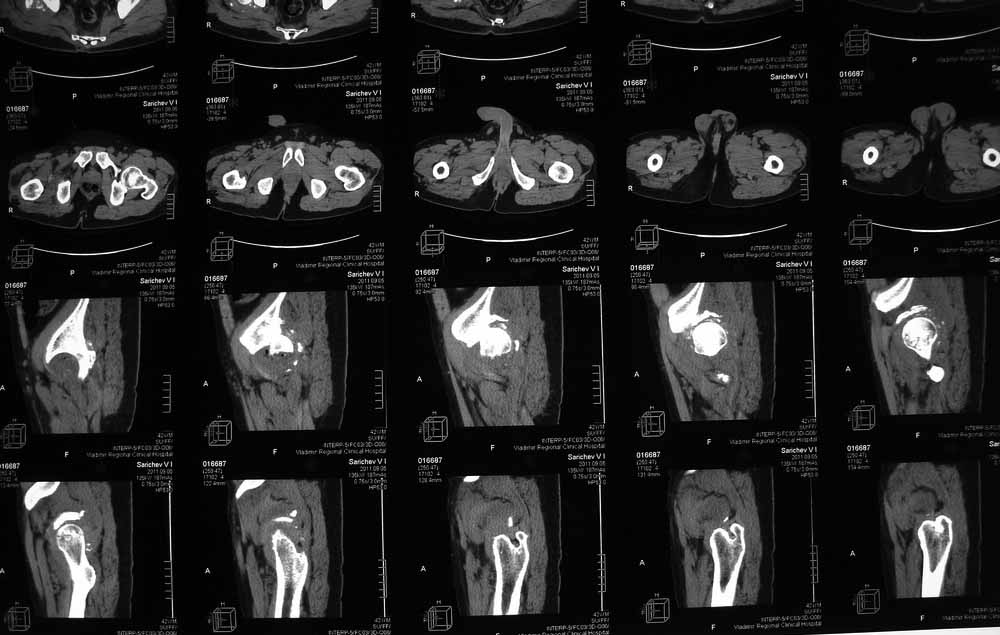

42 года, майор запаса. Травма от 20.06 - ДТП. Лечился в гражданском ЛПУ. Вывих бедра диагностирован только 4 недели спустя. "Тянулся", неоднократно - попытки закрытой репозиции. Попытка открытой репозиции - без результата. Потом опять пытались закрыто, сказали, что вправили, тянулся. После снятия ССВ - опять вывих. Поступил к нам. Сейчас - СРБ больше 10, в ОАК - воспаление. Местно - головка кзади и кверху, укорочение 7, голова подвижна. Отек, незначительная боль в в/3 бедра. Пассивно из наружной ротации выводится, активных движений в ноге нет. Рубец по наружной поверхности верхней трети бедра, без воспаления. Каким образом выполнялось открытое вправление - данных нет. Окончательно снят с вытяжения 2 недели назад.

Структуру головки не очень хорошо видно, есть перелом нижнего отдела головки БК, сломанный задний край небольшой. Срок после травмы 4 недели, молодой возраст. Есть смысл синтезировать ВВ, а дальше посмотреть. Будут проблемы - легче будет протез ставить, ну а если лет 8-10 сустав поработает, то и это хорошо. Если вы уж решили делать протезирование, не мудрите, вполне можно обойтись стандартной вертлужной впадиной с укреплением ее винтами.

В этой ситуации предпочел бы эндопротез, шансы на жизнеспособность головки в таком сроке вывиха исчезающе малы, попытка синтезировать задний край в этих же сроках (ретракция мышц, рубцы) скорее всего приведут к его девитализации с последующим аваскулярным некрозом. Выбор вертлужного компонента проще планировать после 3D, скорее всего можно будет обойтись стандартными предложением, возможно, с котилопластикой.